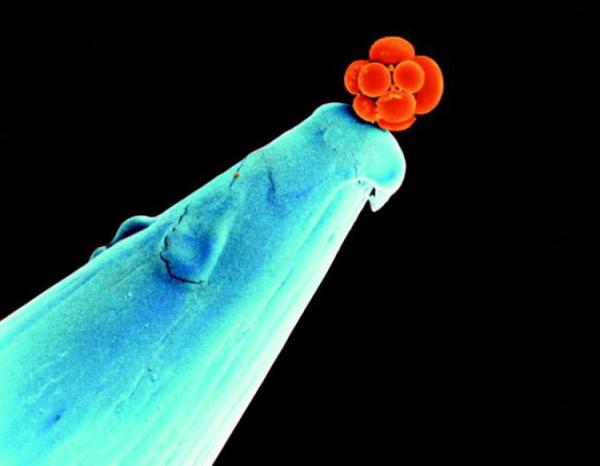

Головоломка дня: что изображено на фото?

Иногда, посмотрев на фотографию, трудно сразу ответить на вопрос: что это такое? Как правило, подобные фотоснимки становятся темой для обсуждения и длительных дискуссий. Это настоящая загадка для фотолюбителей. Отгадайте, что изображено на этом фотоснимке? Какие будут предложения?

Иногда, посмотрев на фотографию, трудно сразу ответить на вопрос: что это такое? Как правило, подобные фотоснимки становятся темой для обсуждения и длительных дискуссий. Это настоящая загадка для фотолюбителей. Отгадайте, что изображено на этом фотоснимке? Какие будут предложения? Есть варианты? Это человеческий эмбрион в возрасте трех дней. В этот период он состоит всего из 16 клеток и может поместиться на кончике иглы.

А вот так он будет выглядеть немного позже: